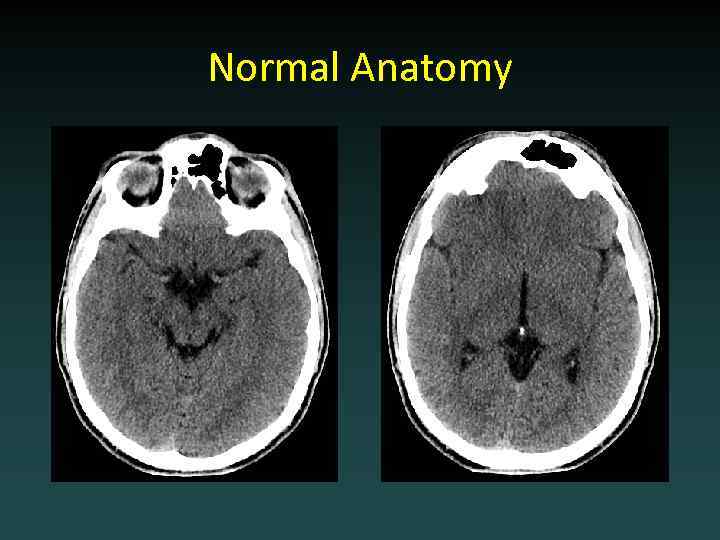

Normal Anatomy